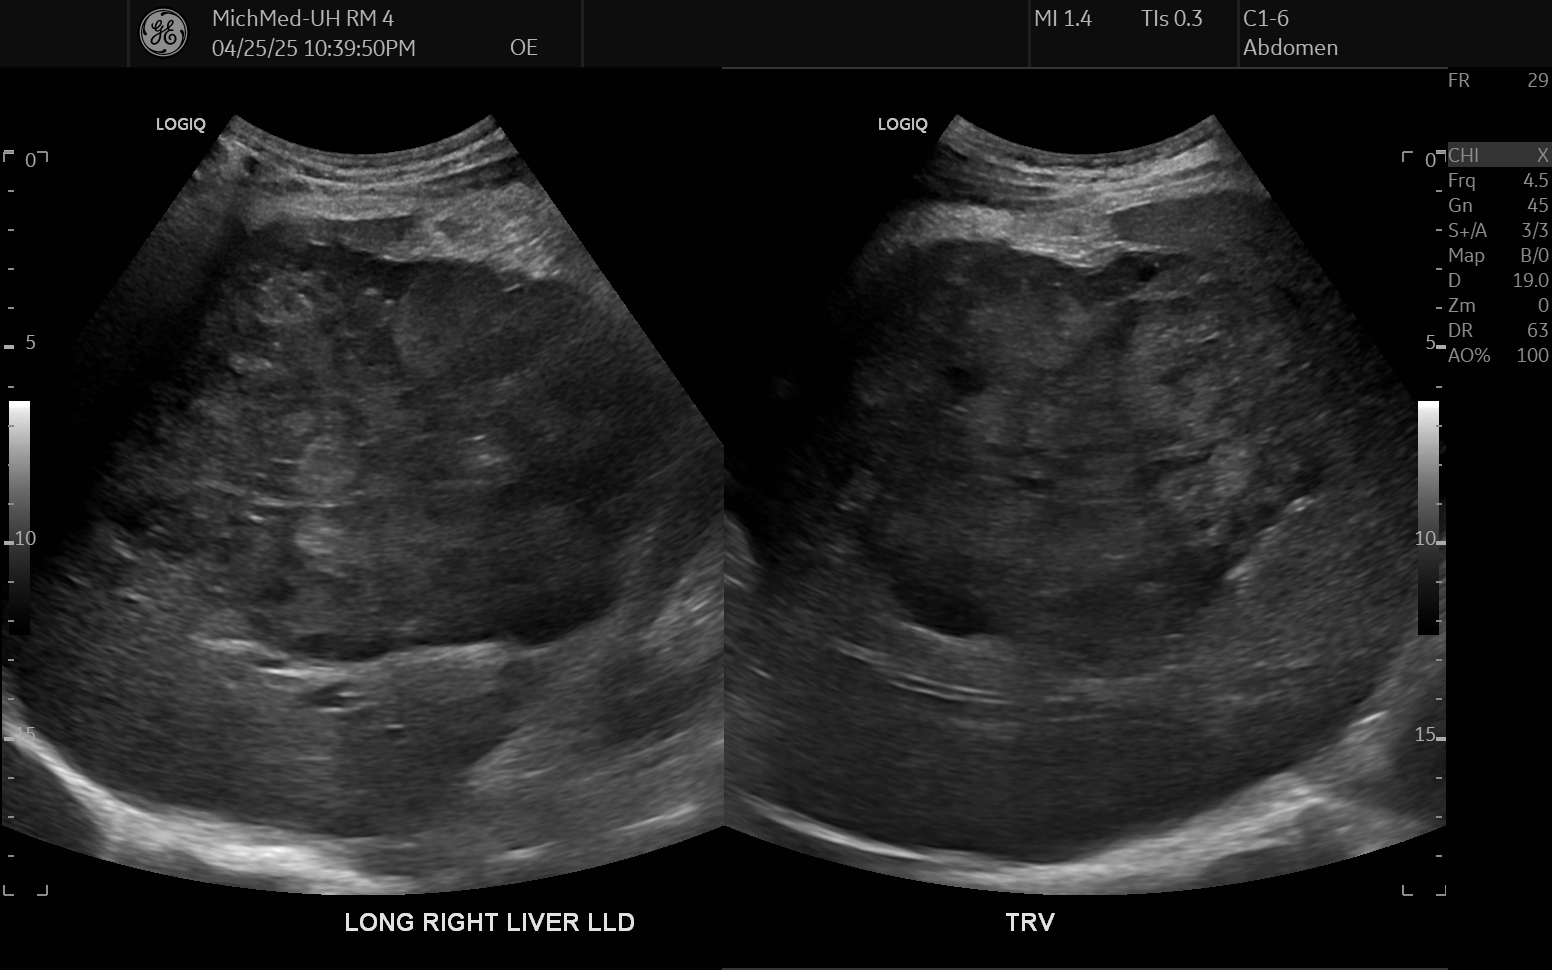

69 M with PMH of HCV cirrhosis & HCC s/p resection in 14 years ago presenting today for a screening ultrasound.

135/73 mmHg / 78 bpm / 16 breaths/min / 96.4°F

sclerae anicteric, no jaundice

CMP wnl, AFP 5